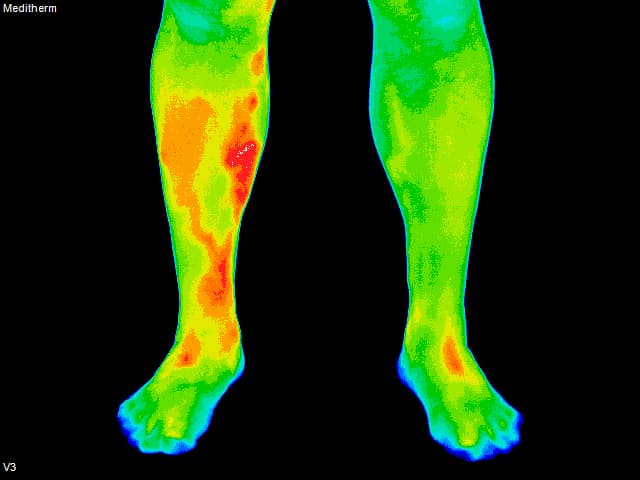

Blood Clot - Back of Leg

Blood Clot - Front View

Blood Clot - Inside ViewWhat Is Thermography?